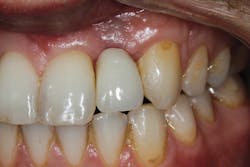

• site development to increase hard and soft tissue for pontic sites in fixed bridge prosthetics (figures 9–14);• correcting bone defects impinging upon anatomical structures after tooth extraction, such as oroantral communication (figure 18); and